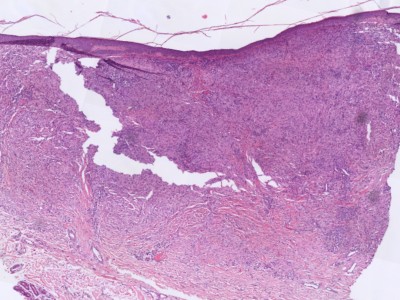

Infiltraat in de dermis bestaande uit histiocyten met een gevacuoliseerd, schuimig cytoplasma en ronde tot ovale kernen met een enkele nucleolus, en vaak met karakteristieke Touton-reuscellen. Daarnaast zijn er in wisselende mate reuscellen, lymfocyten en eosinofiele granulocyten aanwezig. Bij elektronenmicroscopisch onderzoek ontbreken de Birbeck-granula die typisch zijn voor de Langerhans-celhistiocytose. Bij vroege stadia kunnen de Touton-reuscellen en het schuimige aspect van het cytoplasma ontbreken. De cellen kleuren aan met de markers CD68, humaan macrofaag antigeen (HAM) 56 (een epitoop van CD68), factor XIIIa, cathepsine B, KiM1P (een pan-macrofaagmarker), KP1 (een epitoop van CD68) en vimentine, terwijl ze negatief zijn voor S100, CD1a en de macrofaagmarker Mac387.

Histologie juveniel xanthogranuloom Histologie xanthogranuloom

ingescande coupe (zoom) ingescande coupe (zoom)

Histologie xanthogranuloom Histologie xanthogranuloom

PA-Foto's boven: Michael Bonert (Nephron) - Wikimedia (Creative Commons License 3.0)

Hoge resolutie PA-foto's: Kevin Kwee en Afdeling Pathologie MUMC. Klik op de afbeelding om in te zoomen.